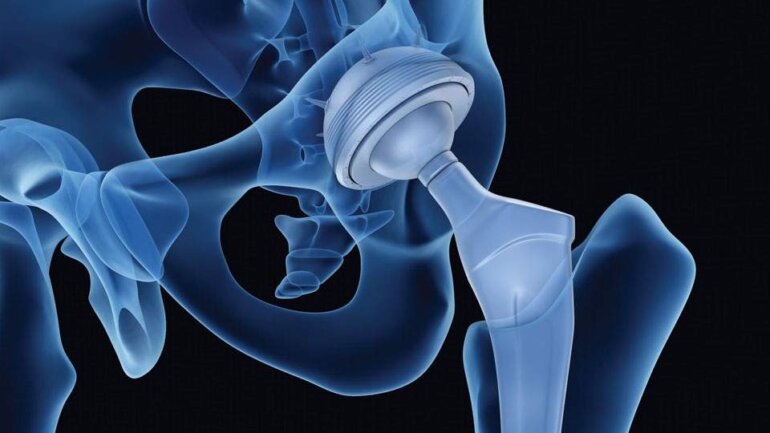

Η ολική αρθροπλαστική γόνατος αποτελεί τη μοναδική οριστική θεραπεία της οστεοαρθρίτιδας τελικού σταδίου.